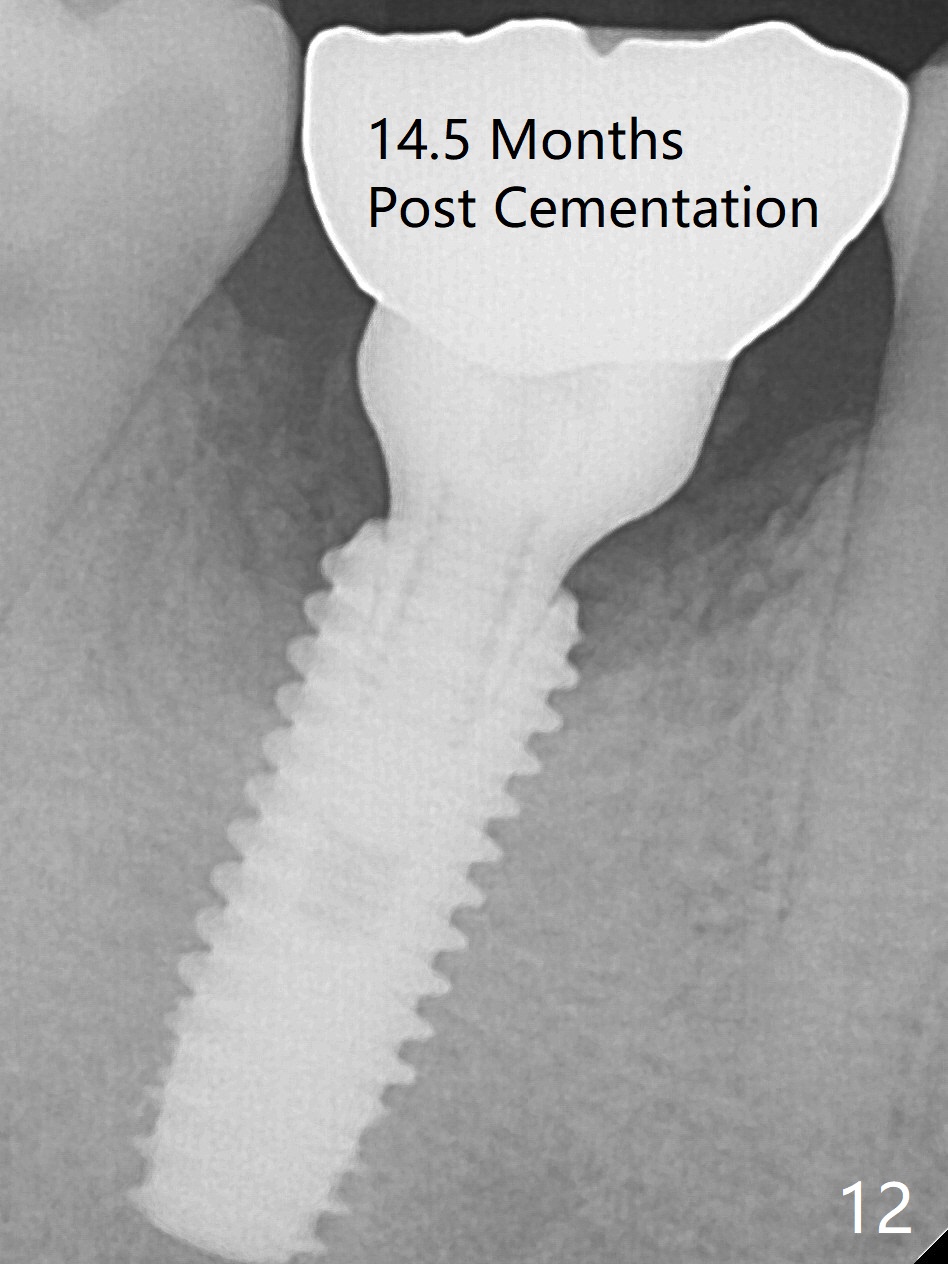

Fortunately no paresthesia is reported postop. Why is the Inferior Alveolar Canal not violated? Fig.7 is a coronal section of CBCT taken for a 40-year-old man at the lower 1st molar (at the septum). At the region, the Canal (brown circle) is close to the lingual plate (L). Because of severe bone loss of the lingual plate of this case (Fig.8 *), osteotomy is intentionally created buccal (green). The deep osteotomy may not contact the Canal, while the hemorrhage may stem from the medullary space (M in Fig.4,7). Bone morphology at the coronal end of the implant apparently changes 4 months postop, suggesting osteointegration (Fig.9). Impression is taken. Bone density around the implant at the crest seems to increase (Fig.10), while there is no soft tissue deficiency 10 months post cementation (Fig.11). The bone appears to regenerate toward the abutment, particularly distally, 14.5 months post cementation (Fig.12). Periimplantitis develops (bleeding on water pik and erythematous and tender buccal gingiva) 1 year 7 months post cementation (Fig.13,14). The 1st three threads are exposed (*). Bone graft with PRF and 6-month membrane or Cytoplast will be needed. Pain disappears 3 days of oral antibiotic. The gingiva looks healthy 1 month later when he returns for bone graft (Fig.15). But the lingual gingival cuff is not so healthy when the crown/abutment is removed (Fig.16 <). Bone graft is not done. For those patients with suboptimal oral hygiene, implants should be placed as low as possible, better with guide for precision.